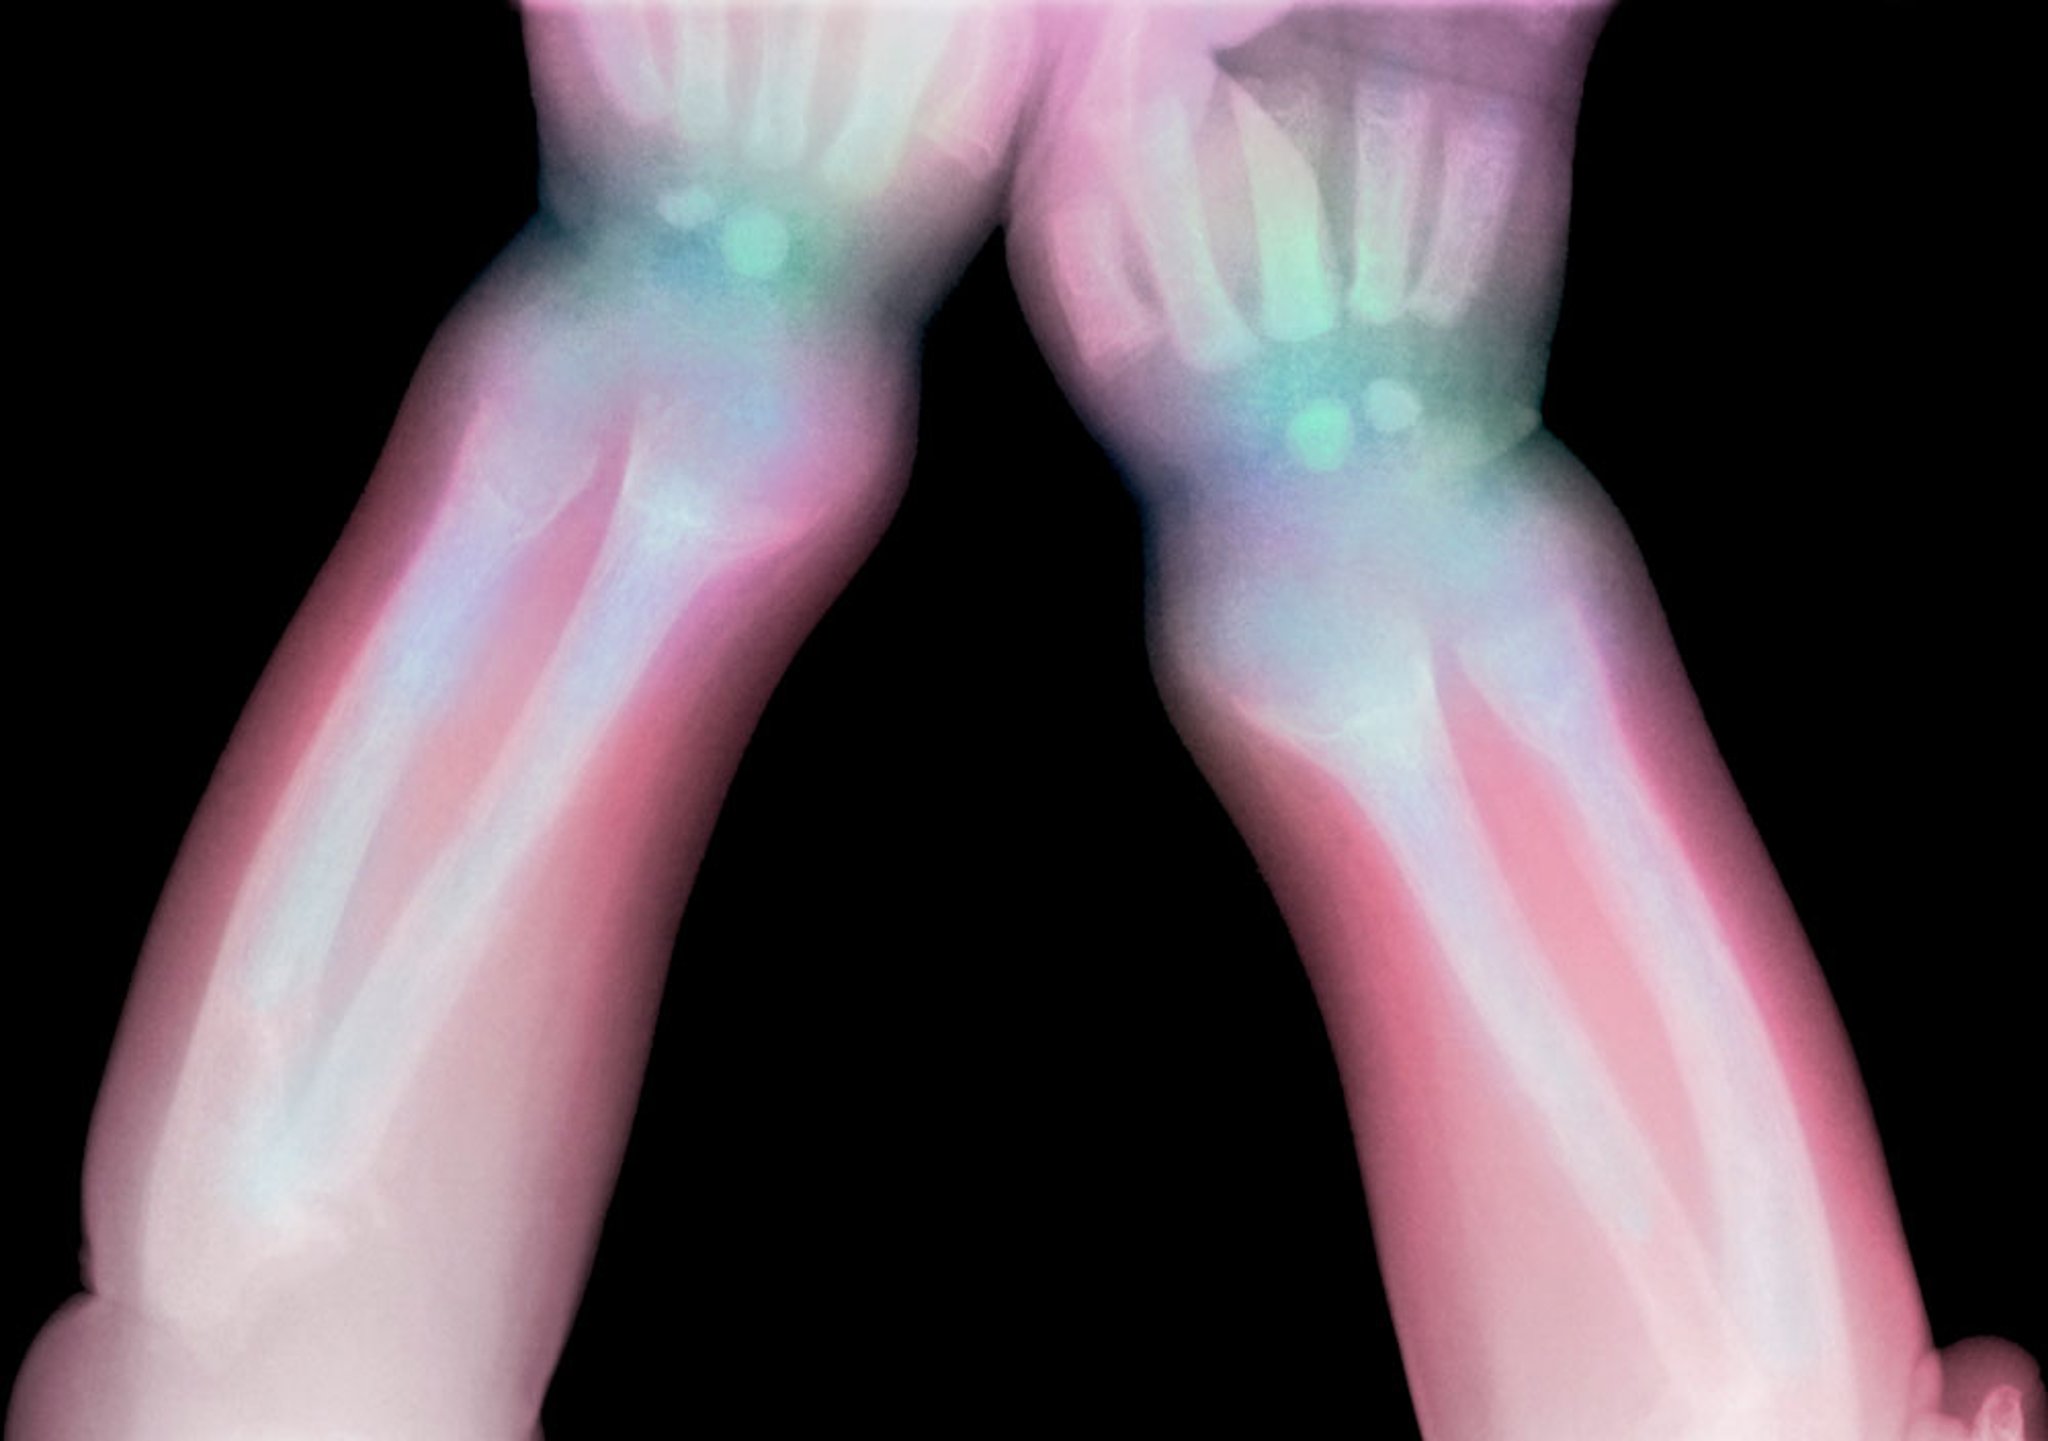

Esta radiografía muestra radiolucidez del radio distal y el cúbito en un niño con raquitismo.